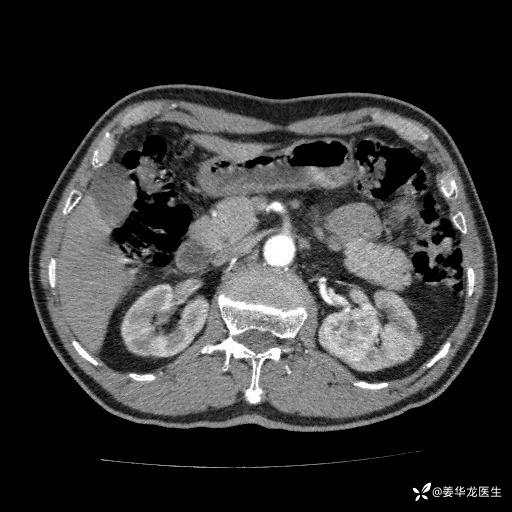

左肾中心型肾门部肿瘤39mm×34mm×36mm,右肾GFR25ml/min,部分切还是全切?

患者75岁老年男性,体重50kg,无高血压、肾病、糖尿病等基础病,检查发现左肾中心型肾门部肿瘤,右肾GFR只有25ml,无肉眼血尿,无镜下血尿。入院验血常规检查均正常,包括肾功能,肌酐102.7umol/L.

二、左肾肿瘤与左肾集合系、左肾动静脉关系密切,左肾部分切除术可行吗?成功率有多大?成功部分切后,肾功能还有多少?